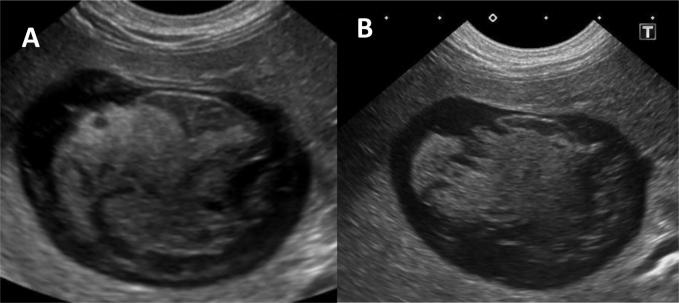

Three months following initial discharge, the patient suffered vomiting episodes, with tremors and lethargy necessitating an emergency revisit. Once more, cranial abdominal pain was detected during palpation, with moderate dehydration (∼5%) was also noted. Repeat haematological examination was requested, with a CBC and serum biochemistry performed. The previous abnormalities detected continued to be present, with a significant increase in the levels of serum alkaline phosphatase (1604 IU/L) and alanine aminotransferase (466 IU/L). This suggested the progression of severe cholestasis. The patient’s serum triglyceride levels had reduced over the prior course of medical therapy, but were still moderately elevated at 14.27 mmol/L (RR 0.6–1.2 mmol/L). Repeat abdominal ultrasound revealed progression of biliary sludge towards gallbladder mucocoele formation (Fig. 2). With the absence of any other significant findings, the abdominal pain was attributed to the gallbladder disease, and an exploratory laparotomy was requested.

Fig. 2.

Progression of gallbladder disease on the repeated abdominal ultrasound. A: Transverse view one month following the first scan. B: Further progression towards mucocoele development three months following initial presentation.